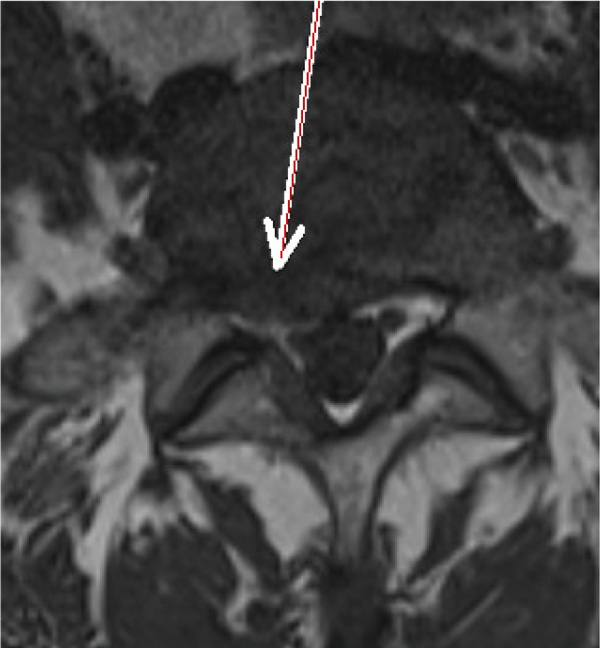

Die folgenden MRT Bilder stammen von einem Patienten mit Bandscheibenvorfall L5/S1. Der Patient ist vorher mehrere Monate arbeitsunfähig gewesen und wurde mit diversen konventionellen Verfahren erfolglos behandelt. Als nächster Schritt wäre eine OP angestanden, die mit der SpineMED® Therapie verhindert werden konnte. Sollten Sie Fragen haben, zögern Sie nicht uns zu kontaktieren, wir bemühen uns um einen Zeitnahen Termin für Sie, und beantworten alle Fragen gerne.

Vor Spinemed